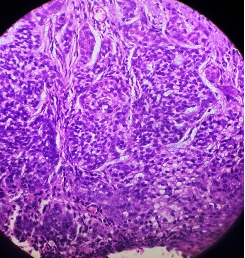

HISTOPATHOLOGY

Section H and E x400. Mass in the wall of the small intestine in a 72 year old male patient who presented with frequent diarrhoea. Make you diagnosis.